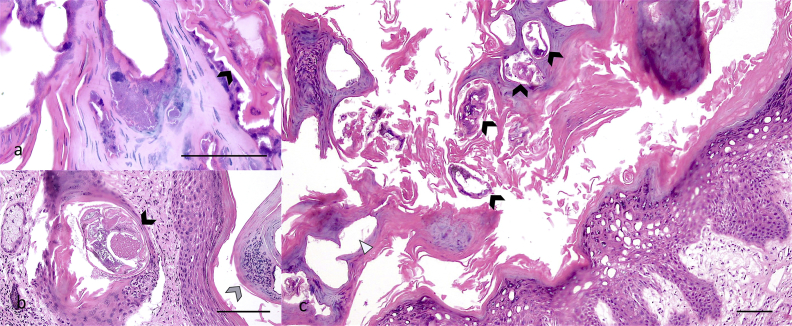

Fig. 2.

a-c. Microphotograph of skin section of a mature female Coendou quichua with severe sarcoptic mange. a) Intralesional cocci observed surrounding parasitic tunnels, with mite (arrow head 20X). b) Intralesional mite (black arrow head) and pustule (grey arrow head 10X), and c) several tunnels with (black arrow heads) and without (white triangle) mites in the stratum corneum (4X). All bars = 100 μm. Haematoxylin and Eosin stain.